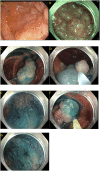

Most colorectal cancers arise from adenomatous polyps and sessile serrated lesions. Screening colonoscopy and therapeutic polypectomy can potentially reduce colorectal cancer burden by early detection and removal of these polyps, thus decreasing colorectal cancer incidence and mortality. Most endoscopists are skilled in detecting and removing the vast majority of polyps endoscopically during a routine colonoscopy. Polyps can be considered "complex" based on size, location, morphology, underlying scar tissue, which are not amenable to removal by conventional endoscopic polypectomy techniques. They are technically more challenging to resect and carry an increased risk of complications. Most of these polyps were used to be managed by surgical intervention in the past. Rapid advancement in endoscopic resection techniques has led to a decreasing role of surgery in managing these complex polyps. These endoscopic resection techniques do require an expert in the field and advanced equipment to perform the procedure. In this review, we discuss various advanced endoscopic techniques for the management of complex polyps.